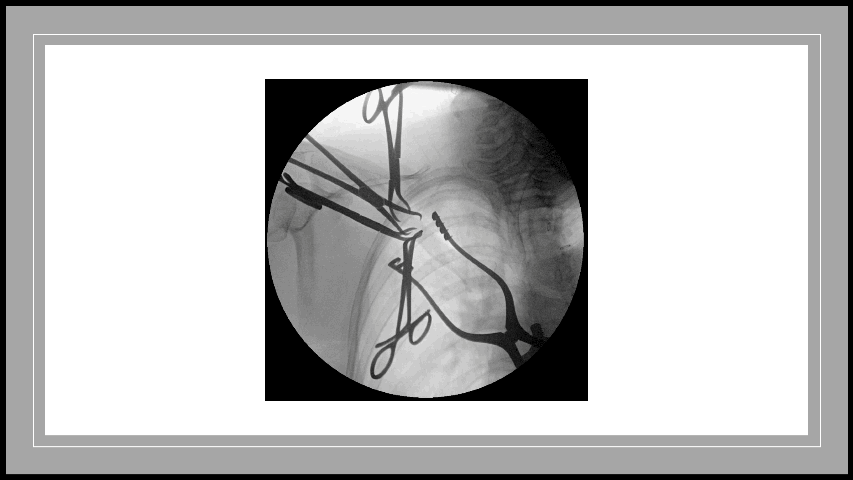

![]() Distal radius fracture | ![]() Bilateral total hip replacements | ![]() Fluoroscopy of clavicle fixation | ![]() Intra-articular distal humerus fracture |